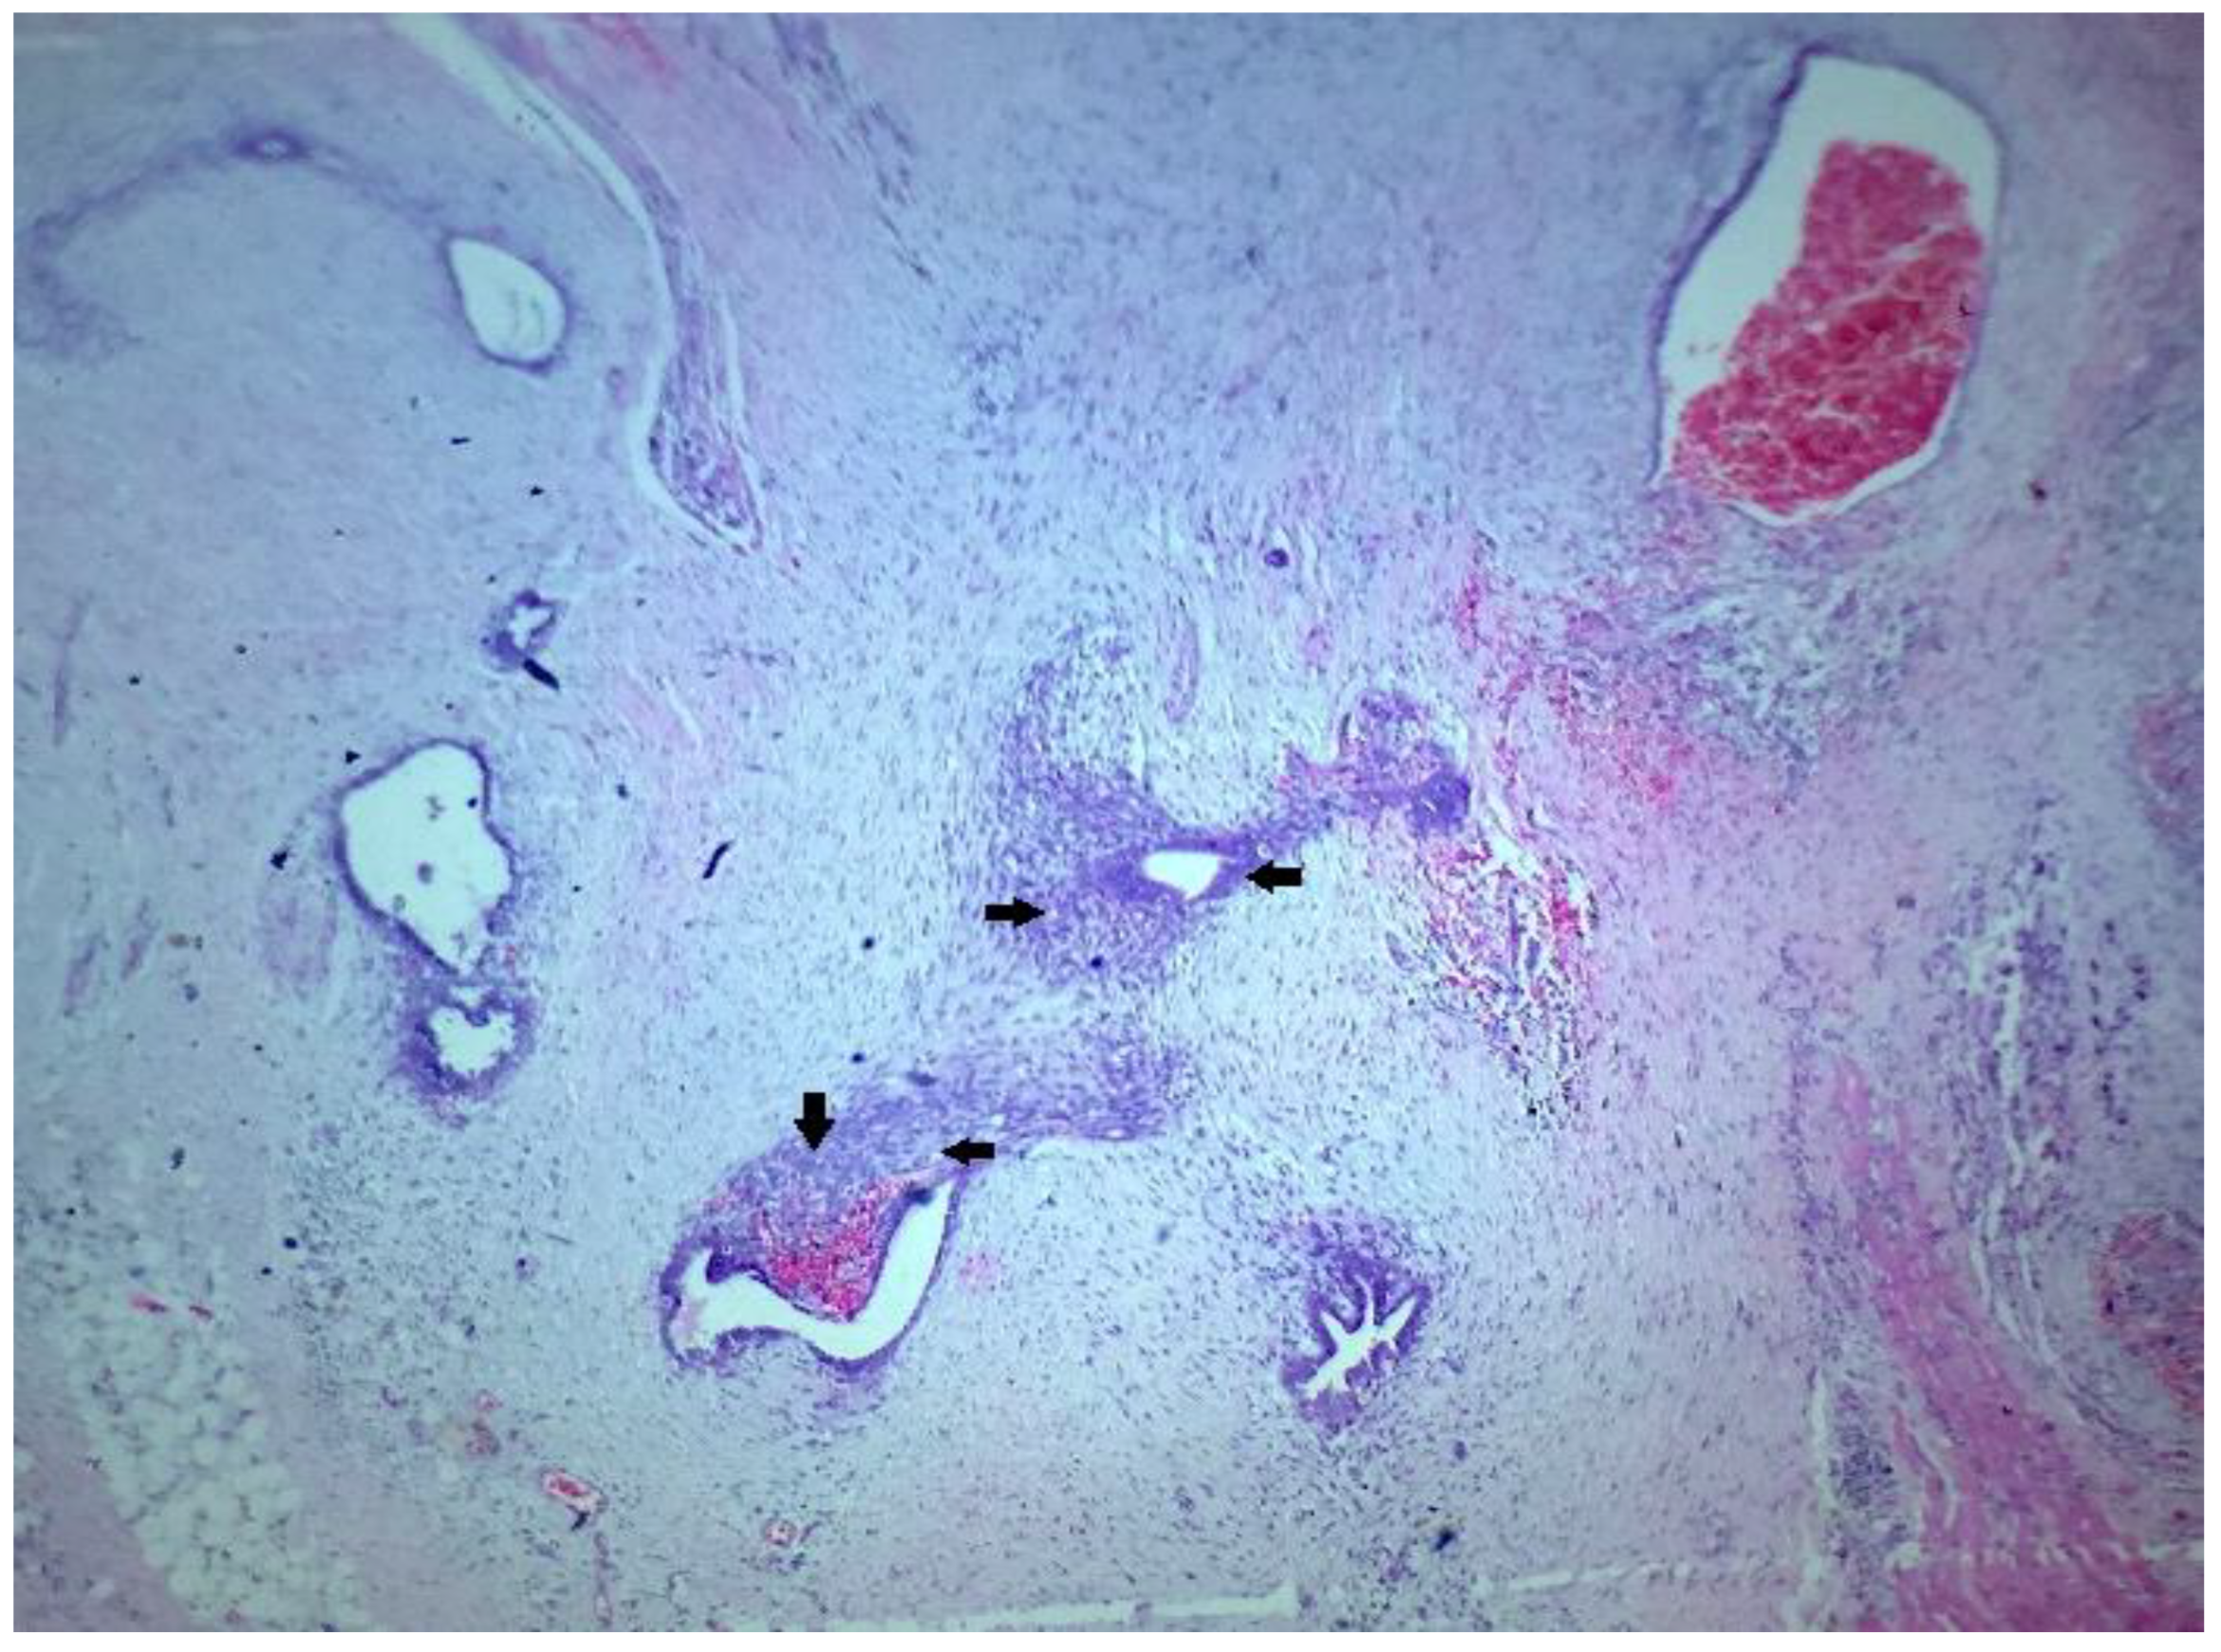

2. Case Presentation